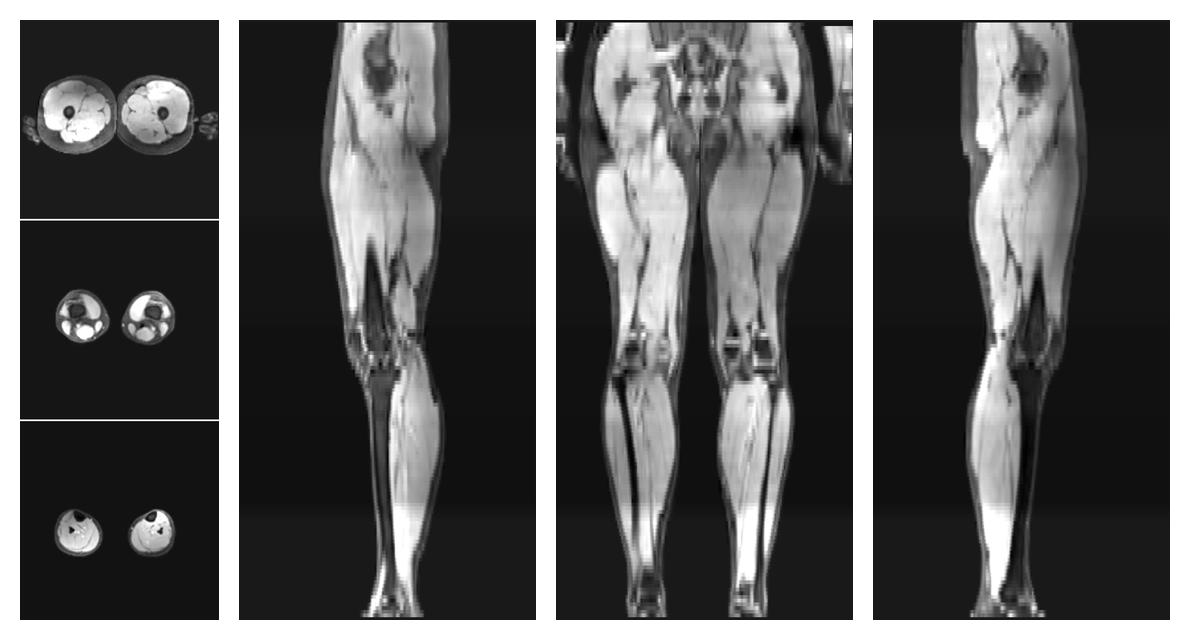

• Water only signal

The water part of the acquired multi-echo spin echo data.